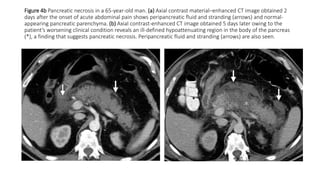

Figure 4b Pancreatic necrosis in a 65-year-old man. (a) Axial contrast material–enhanced CT image obtained 2

days after the onset of acute abdominal pain shows peripancreatic fluid and stranding (arrows) and normal-

appearing pancreatic parenchyma. (b) Axial contrast-enhanced CT image obtained 5 days later owing to the

patient’s worsening clinical condition reveals an ill-defined hypoattenuating region in the body of the pancreas

(*), a finding that suggests pancreatic necrosis. Peripancreatic fluid and stranding (arrows) are also seen.